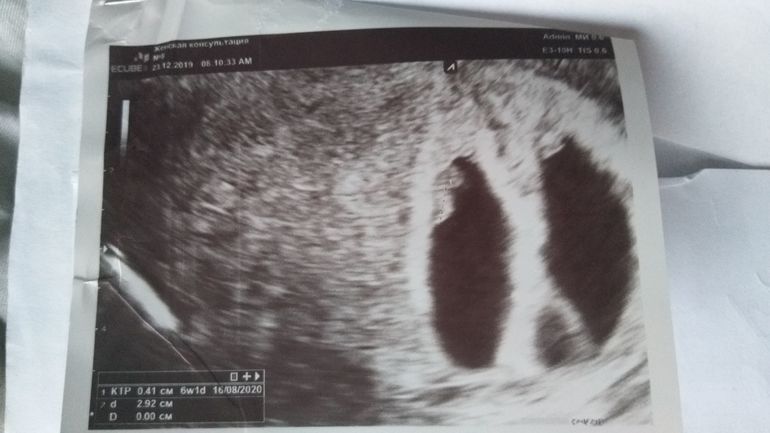

Наши два сердечка❤💙Первое узи 6 нед. 3 дня по мес